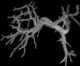

Caroli disease (communicating cavernous ectasia, or congenital cystic dilatation of the intrahepatic biliary tree) is a rare inherited disorder characterized by cystic dilatation (or ectasia) of the bile ducts within the liver. There are two patterns of Caroli disease: focal or simple Caroli disease consists of abnormally widened bile ducts affecting an isolated portion of liver. [Source: Wikipedia ]